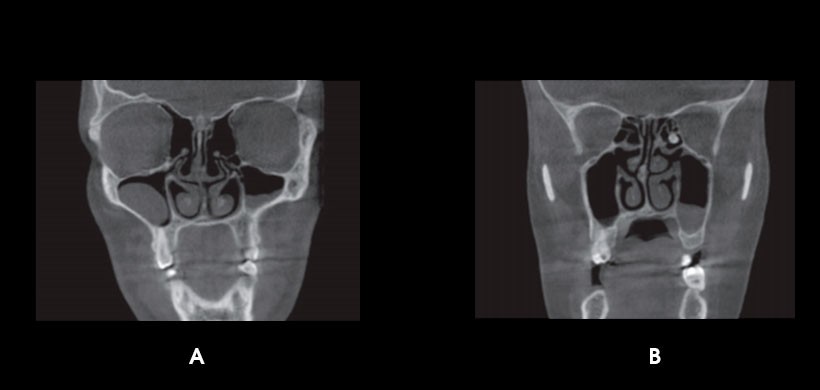

Fig 3. CBCT. A) Sinusitis en seno frontal. B) Periostitis en seno maxilar derecho.